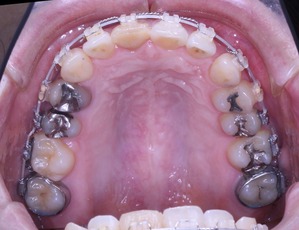

治療開始から3年経過した現在の状況です

上の歯列はどうでしょうか?

このように長期的な歯列矯正治療になる場合は患者さんの理解も必要になってくると思います。

通常の症例が抜歯部位を変更するだけで、難症例になってしまいます。